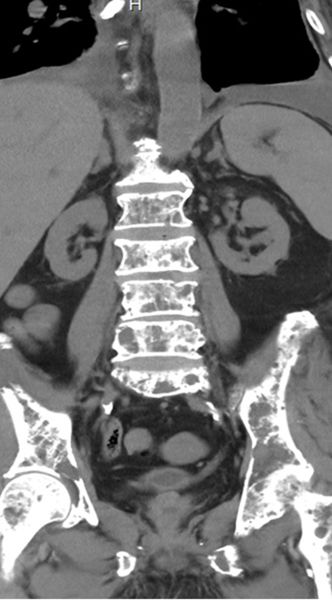

▲X光影像顯示,病人罹患多發性骨髓瘤,腰椎及胸椎已出現多節壓迫性骨折。 (圖/記者蔣彤雲攝)

病人住院期間,醫療團隊進一步評估發現,他的腎功能惡化情形與原有慢性腎臟病進展並不相符,研判可能另有潛在病因,於是安排免疫蛋白電泳檢查,檢出異常免疫球蛋白,病人長期有腰背疼痛情形,影像檢查顯示腰椎與胸椎已有多節壓迫性骨折,並合併高血鈣表現,臨床高度懷疑為多發性骨髓瘤。